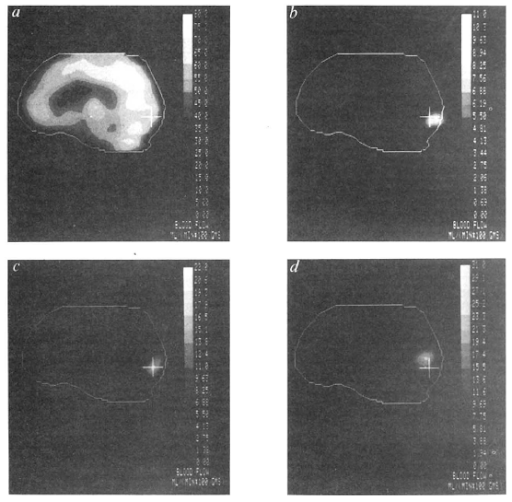

自 第一篇PET脑功能定位研究 起,PET技术在脑功能成像研究中取得了巨大的成功。但PET本身的局限也使得人们在探索新的脑影像技术。PET的局限主要是两点:放射性和时间分辨率低。放射性自不必提。就时间分辨率讲,扫描一幅PET图像需要几分钟的时间。这就使得PET只能用来研究稳态的神经活动。 1990年,Ogawa提出可以使用MRI测量内生的血氧水平依赖信号 (BOLD)来间接测量脑活动 (Ogawa et al., 1990)。两年后,第一篇使用BOLD效应的人类fMRI文章发表 (Kwong et al., 1992)。fMRI最大的卖点自然是动态性,因此文章的标题特别强调了"dynamic"。文章最主要的实验是一个简单的视觉实验。值得一提的是,这篇文章也是第一个采用block design实验设计的fMRI研究。使用被试看视觉刺激时的fMRI图像减去基线时的图像,可以很清楚的显示出视皮层的激活 (下图左)。而更重要的是,如果提取视皮层的信号,还可以清楚的显示出视皮层活动随任务变化的动态过程 (下图右)。 此外,这篇文章还做了另外两个实验。实验二是使用兔子做的验证实验。实验操纵兔子呼吸的空气的O2和CO2的比率,并观测到BOLD发生随CO2含量变化。这表明了观测到的信号确实是对血氧水平敏感的信号。而实验三做了一个人类的手动任务,得到了运动皮层的激活。这表明所观测到的BOLD效应并不只局限于视皮层。 这篇文章背后有很多故事,可以在 这里 看到一些。更有意思的是,实际上在两个月里有三篇人类BOLD fMRI的研究相继发表。Ogawa先提出了BOLD信号的想法,随后包括Ogawa在内的三个组同时做人的BOLD成像。这时时间很重要。Kwong的文章发表在1992年6月的PNAS上,Ogawa的文章发表在7月号。但投稿日期Kwong只早了5天。但最早出版确是Milwaukee的 wisconsin  medical school的Bandettini等人的文章,在6月的Magnetic Resonance in Medicine。但仔细看投稿日期,Bandettini投稿最晚,但选择了MRM以求快速发表。不过所有人都承认idea是Ogawa的。 Bandettini PA, Wong EC, Hinks RS, Tikofsky RS...

之前一直以为这篇文章 (Fox et al., 1986)是第一篇使用功能成像技术定位脑功能的研究报告。但搜索文献后发现其实并不是。在20世纪80年代初已经有很多使用PET研究精神疾病的研究,比如 (Baxter et al., 1985)。Fox和Raichle在1984年也曾发表过文章研究视觉刺激呈现频率对视皮层局部脑血流量的影响 (Fox & Raichle, 1984)。但仔细读过这篇文章后,觉得这篇文章才更接近于目前意义上的脑成像研究。 首先是PET技术空间分辨率问题。更早的研究大都使用感兴趣区域分析,可能与PET技术固有的空间分辨率有关。虽然PET图像采集本身的分辨率可以达到几毫米,但由于放射性扩散和图像采集技术等的限制,PET图像的空间分辨率要低于1厘米。但Fox et al.认为,如果把PET图像扑捉到的神经活动看成一个点的空间概率分布函数,1厘米以上的概率分布宽度并不影响定位相距几毫米的神经区域。也就是说,如果两个神经区域的距离小于1厘米,通过合理的实验设计也是可以分别定位这两个区域的。理论上似乎好理解,但更主要的是要给出漂亮的结果。 于是这个研究给被试观看3种大小的视觉刺激。对每个被试分别记录了这三个条件以及相对应对照条件的的PET脑血流量图像。之前的动物研究和病人研究已经知道视野不同位置的刺激会激活视皮层的不同区域。与这些结果对应,这篇文章发现呈现在视野黄斑区的刺激激活最靠后的部分,而最外周刺激激活的区域最靠前 (下图b到d)。三个激活点在AC-PC轴方向的距离小于1厘米。但是位置差异还是可以很清楚的显示出来。 这篇文章的另一个重要贡献是提出设置对照条件,使用相减处理PET图像结果,以达到定位的目的。这基本打下了脑成像研究的逻辑基础:设计对照条件,相减和定位。这种研究思路一直是脑成像研究的主流。 如何设置对照条件是另一个问题。这篇文章的对照条件是“静息状态" (resting-state)。从心理学上讲静息状态并不是一个好的对照条件,因为和任务态的差别太大。但正是静息态作为对照条件的频繁使用,才使得Marcus Raichle后来可以定义一个在静息态时激活高、而在做各种任务时激活下降的默认网络 (Raichle et al., 2001)。 Baxter LR Jr, Phelps ME, Mazzi...